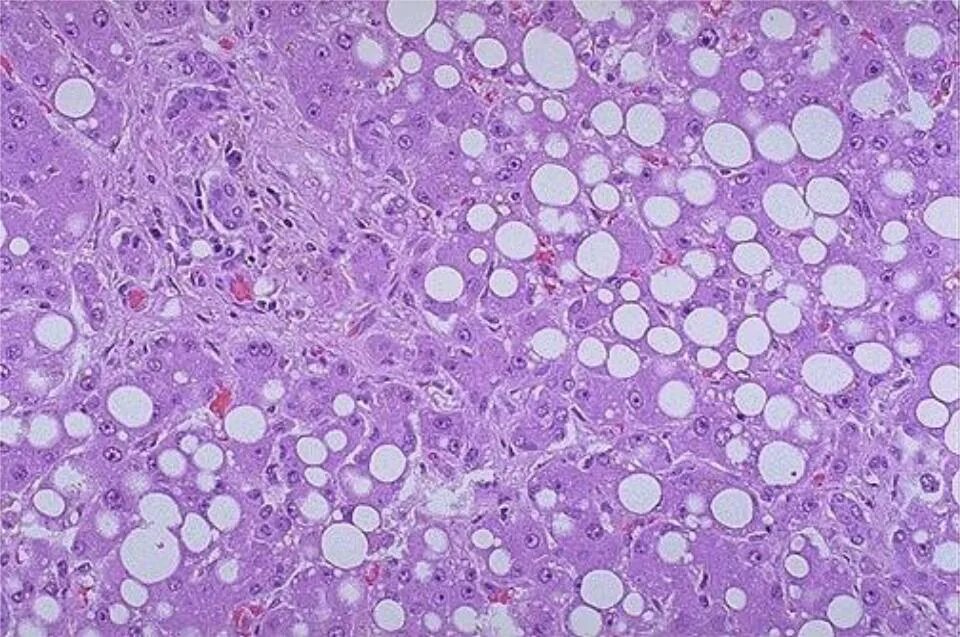

Патан пф